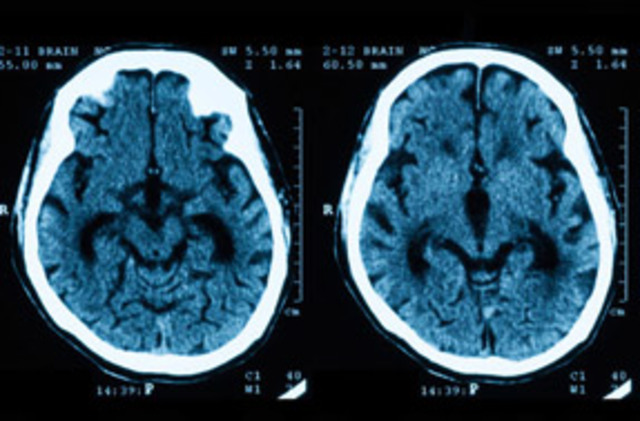

en 1970 fue el físico HOUNSFIELD quien trabajo desarrollando un

corte tomográfico sectorial sobre la cabeza de un ser humano.

• IMAGENES CRANEALES

IMAGENES CRANEALES